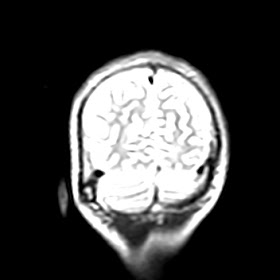

Radiological images: